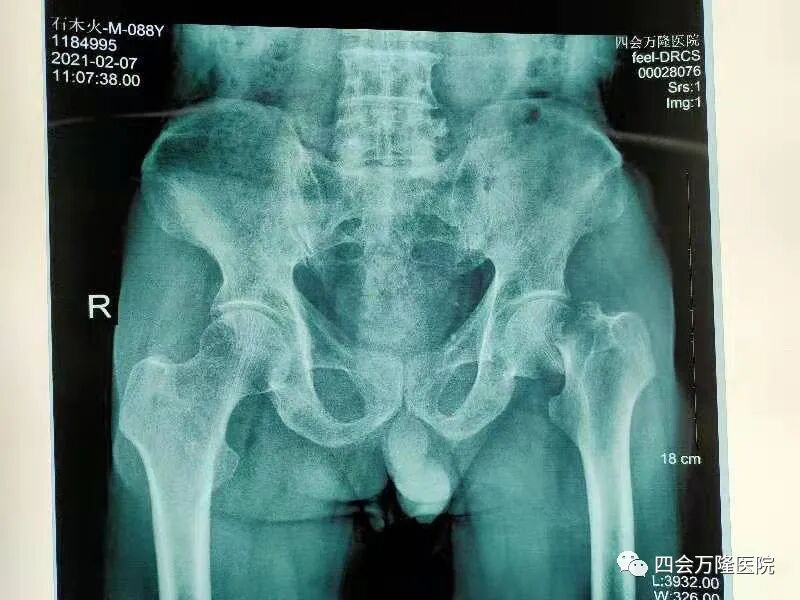

2月7日,88岁高龄的李爷爷(化名)一不小心在家摔倒了,本以为休息两天便好,可李爷爷左髋部疼痛难忍,活动受限,站立不得,行走不能,于是家属呼叫救护车送到四会万隆医院骨科就诊。

股骨颈骨折属于髋部骨折,髋部骨折被喻为人生最后一次骨折,因为其死亡率极高。据国际骨质疏松基金会的报告显示:发生髋部骨折的老年人,一年内的死亡率可达20%-24%。

(术前查体片)